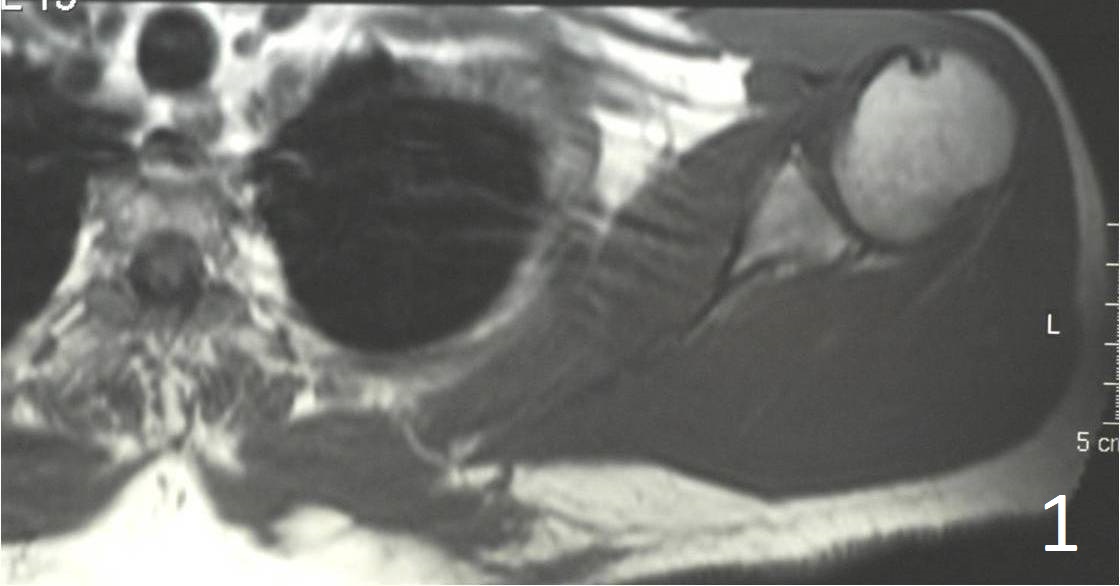

Large mass with heterogeneous signal intensity (Fig. 1, 2)

Fig. 1, 2 Axial MRI of shoulder shows a lesion in the subcutaneous tissue along the postermedial border of the scapula.